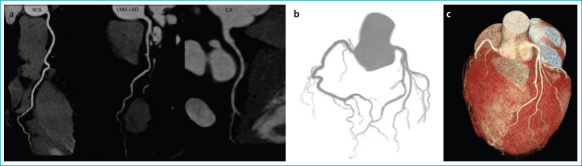

Methods: We retrospectively evaluated a total of consecutive 688 patients who were either asymptomatic but had a positive family history or had typical or atypical symptoms suggesting the presence of CAD. They all underwent CCTA examination with multiplanar reformat (MPR), maximal intensity projection (MIP), and myocardial three-dimensional (3D) volume rendering (VRT) images were obtained. We calculated CCS, coronary artery plaque stenosis degrees, the number of main coronary arteries involved and the EFVs for each patient. Finally, the relationship between the EFVs and all other parameters was analyzed by performing the Pearson and Spearman correlation analysis.